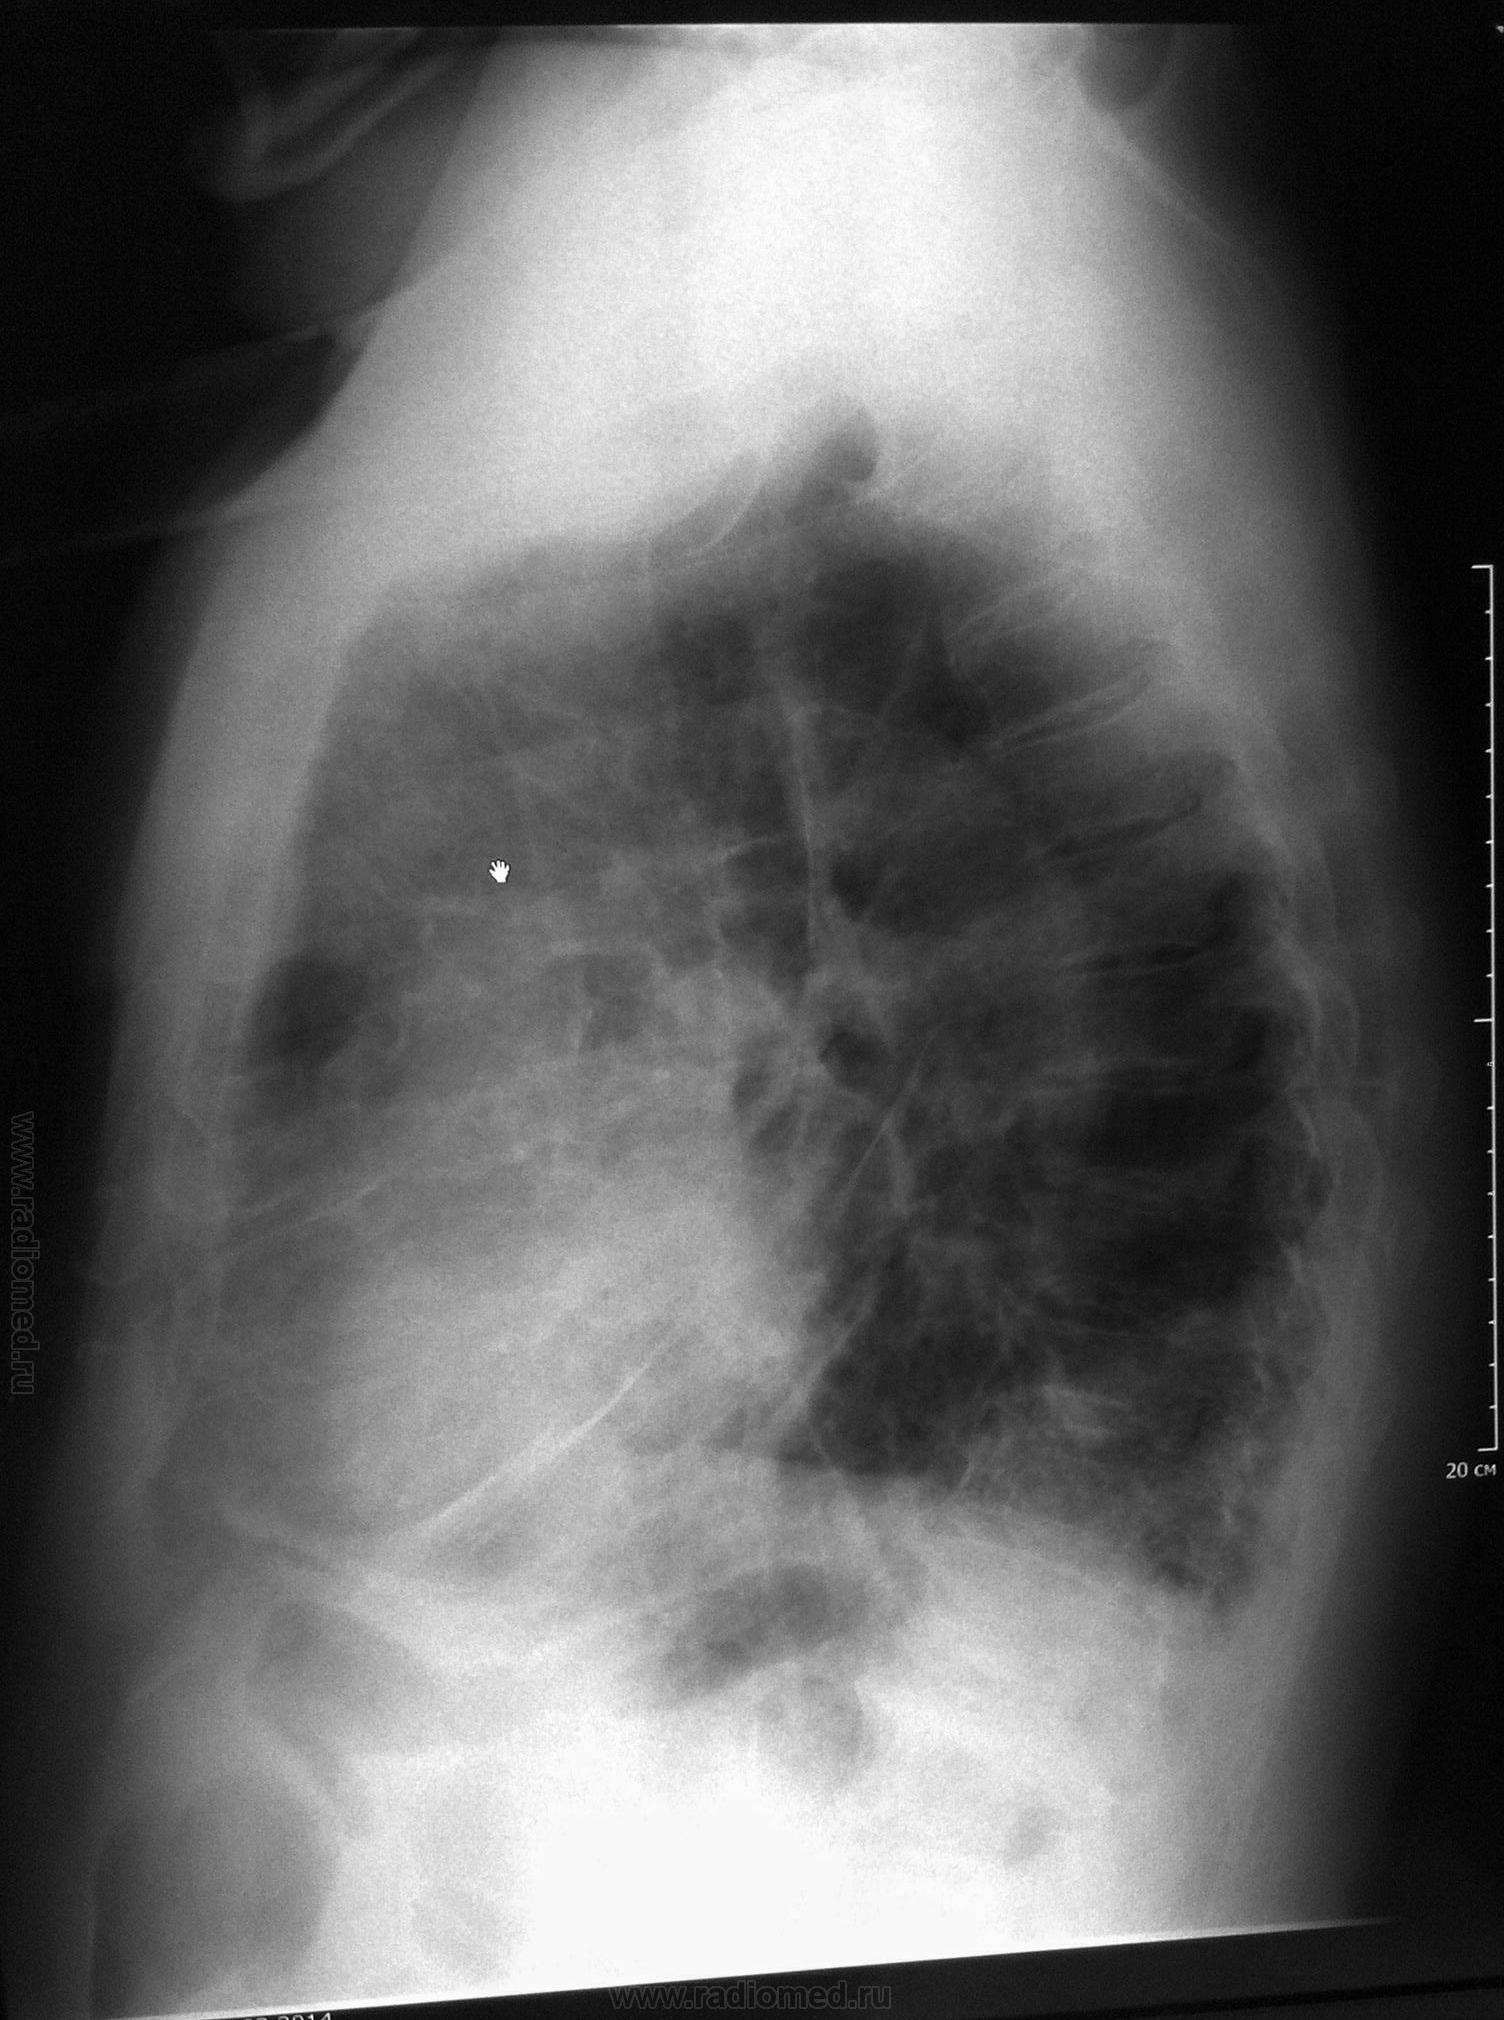

М., 71г., выявлен по флюорографии, направлен с д-зом: ХНЗЛ, плевропневмония слева. Госпитализирован с ХОБЛ, обострение. Клинически - не лихорадит, одышка, кашель, кровохарканье. Выполнена ФБС: картина атрофич. эндобронхита. Пришел на контроль.

Фото с телефона, извините за качество

Прошу прощения, не поняла, как повернуть фото. Первые 3 снимка 31.03.2014г. Затем контроль 7.04.2014г., томограммы в этот же день на предмет исключения центрального рака.

конечно, смотреть сложно в повернутом виде, поэтому можно только предположить, но я согласна с Вами, что здесь нельзя исключить центральный с-ч, даже при наличии отрицательных данных ФБС - широкий левый корень, расширенное верхнее средостение и гиповентиляция в нижней доле слева. Поэтому, рекомендую КТ и консультацию онколога повторно.

Присоединяюсь-цикличность левого корня и гиповентиляция верхнего сегмента нижней доли.КТ поставит точку

Динамика отрицательная.Впечатление о нижнедолевой пневмонии слева, осложнённой гиповентиляцией. Так что и рак - не исключён, с параканкрозным пневмонитом

Опухоль нужно искать, нижняя доля слева в гиповентияции, средостение влево уезжает, это не пневмония

Уважаемые коллеги, спасибо за помощь! С 31.03. по 7.04. Лечили аугментином, амброксолом, сальбутамолом и т.д. Клинически больному не хуже, пришел на контроль перед выпиской. Рекомендовала КТ для исключения центрального преимущественно эндобронхиального рака нижней доли левого легкого, осложненного гиповентиляцией S6,10. КТ сделали, заключение: пневмония в нижней доле левого легкого, ст. разрешения. Бронхоэктазы. Пуль монологи довольны, больной выписан.